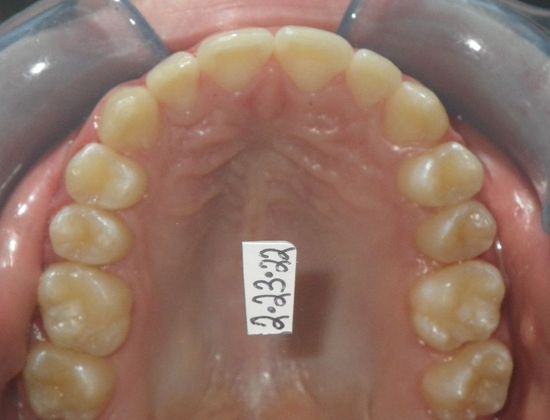

This patient had an upper right permanent cuspid that was impacted and would need uncovering by oral surgeon who would place bracket with chain to help enable us to tease the permanent cuspid into its proper position. She also had a permanent 2nd Molar that was impacted due to improper development of 3rd molars and the oral surgeon could remove them at the same time as uncovering of the permanent cuspid. After uncovering and removal of lower 3rd molars, we would begin comprehensive straight wire orthodontic treatment.